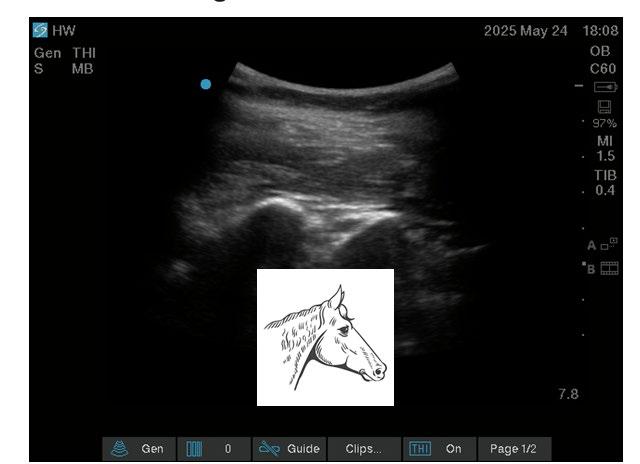

Another focus for AI in anaesthesia lies in real-time analysis of ultrasound scanning.[8] Multiple algorithms have been developed to segment and apply colour to greyscale ultrasound live images. Despite promising progress, the evidence base gathered to assess and appraise the utility of these various tools remains insufficient. Studies are too heterogenous, use differing performance metrics and ground truth definitions, or are simply not made public due to commercial sensitivity.[9]